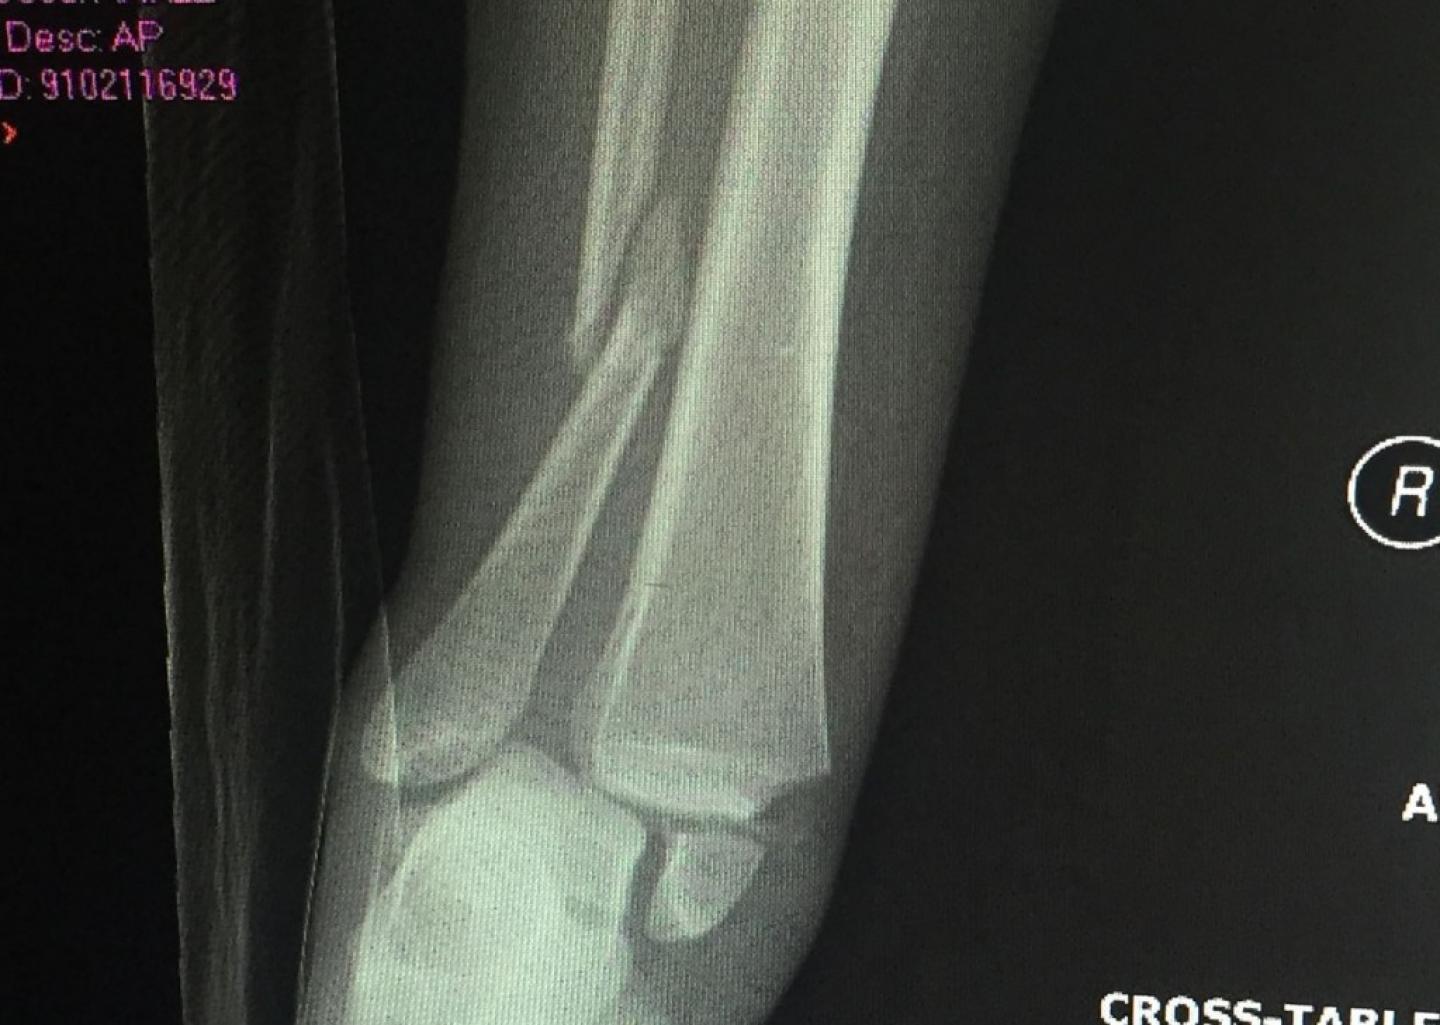

During the first game of the season, Rickard had landed a tackle and was attempting to recover when her teammate tackled an opposing player onto her. The force of the falling player broke Rickard's tibia and fibula and tore the ligament keeping the two taut.

Upon her arrival in Charlotte, Rickard rushed into surgery. The results: 12 screws and a plate in her leg.

Photo courtesy of Lainey Rickard

Although, two screws have been removed since surgery, Rickard is still recovering from the reconstruction of her bones and ligaments. It took her about four months before she was able to walk without her knee scooter or crutches.